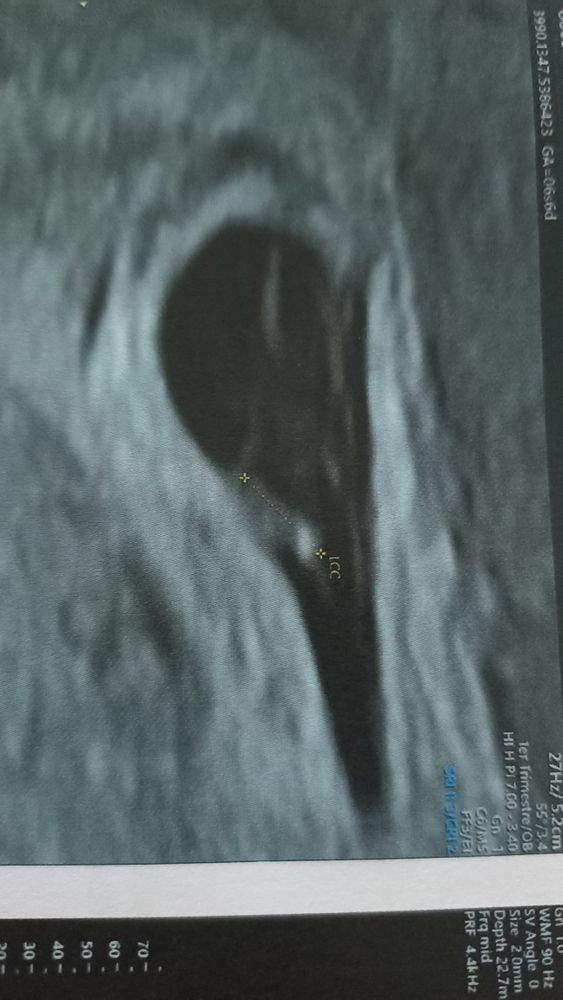

Интересно попробовать, тем более, что скоро узнаю пол точно) сделала всё, как вы сказали, только вот не могу понять, на моем фото хориона больше по правой стороне?

Это 8+4